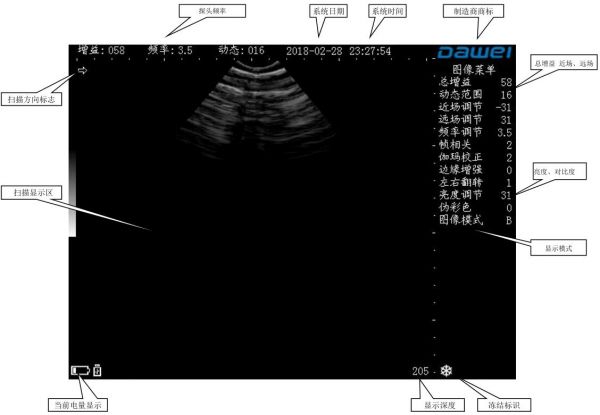

在诊断部位涂以适量的接触剂(医用超声耦合剂),将探头声窗紧密地接触在诊断部位。屏幕将显示出组织的截面声像图,适当移动探头,寻找和确定探测深度的最佳位置;同时,适当调节亮度、动态、总增益、近场、远场,以获得诊断部位的最佳截面声像图。